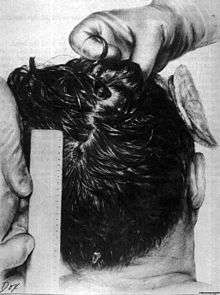

| GRAPHIC WARNING: a color picture of President Kennedy's head wound taken at the beginning of the autopsy |

|---|

A picture of President Kennedy's head taken at the beginning of the autopsy |

- The wound to the back of the head is described by the Bethesda autopsy as being a laceration measuring 15 by 6 millimetres (0.59 in × 0.24 in), situated to the right and slightly above the external occipital protuberance. In the underlying bone is a corresponding wound through the skull showing beveling (a cone-shaped widening) of the margins of the bone when viewed from the interior of the skull.[8]

- The large, irregularly shaped defect in the right side of the head (chiefly to the parietal bone, but also involving the temporal and occipital bone) is described as being about 13 centimetres (5.1 in) wide at the largest diameter.[8]

- Three fragments of skull bone were received as separate specimens, roughly corresponding to the dimensions of the large defect. In the largest of the fragments is a portion of the perimeter of a roughly circular wound presumably of exit, exhibiting beveling of the exterior of the bone, and measuring about 2.5 to 3.0 centimetres (0.98 to 1.18 in). X-rays revealed minute particles of metal in the bone at this margin.[8]

- Minute fragments of the projectile were found by X-ray along a path from the rear wound to the parietal area defect.[9]